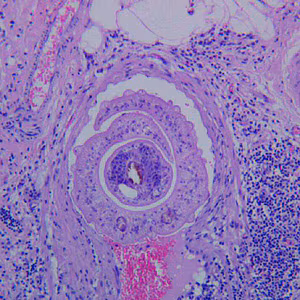

A 35-year-old woman went to her health care provider with complaints of abdominal pain, cramps and diarrhea. She told her doctor that she had recently returned from a business trip to Mexico. Stool was collected in 10% formalin and polyvinyl alcohol (PVA) for routine ova-and-parasite (O&P) examination.